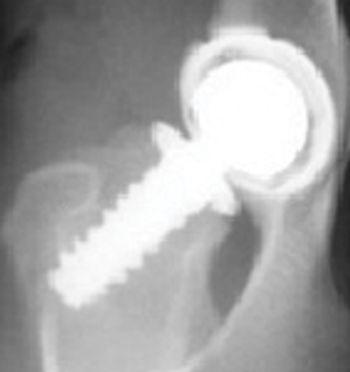

Coxofemoral luxation is the most commonly luxated joint in dogs, accounting for 90% of all luxations. It is usually the result of trauma or severe hip dysplasia with 78% being craniodorsally luxated.

The coxofemoral joint is a ball and socket joint. Normal stability of the hip is provided through a combination joint capsule, ligament of the head of the femur and dorsal acetabular rim. In addition, the joint fluid and acetabular labrum including the ventral acetabular ligament and extraarticular soft tissue structures such as the gluteals, adductors and abductors of the hip joint provide secondary stability.